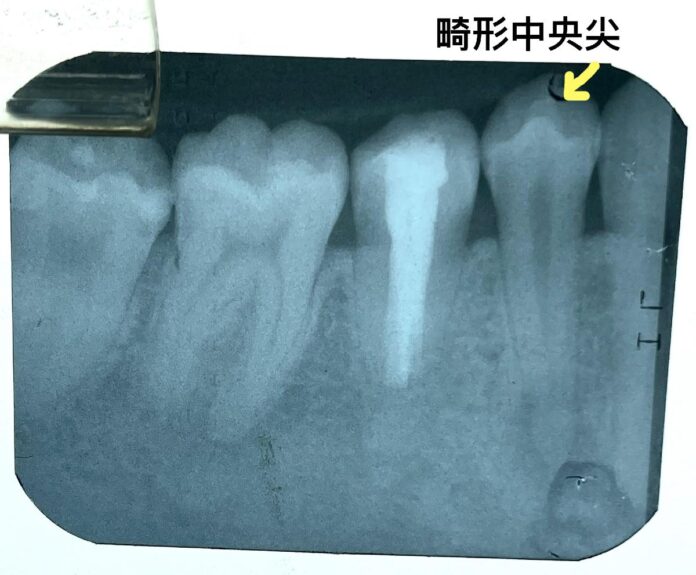

醫師往口內檢查發現,原來下顎小臼齒的咬合面中央多了一個結節;不意外地,在上顎小臼齒上,也有對稱性的發生。此一結節名為畸形中央尖(central cusp deformity),呈圓錐狀突起,高約2-3mm,看起來已受到咬合磨損,根尖X光片則顯示出因牙髓神經壞死而導致的根尖周圍感染。

潘老師接受醫師建議進行根管治療,經過密集回診,從X光片上見到根尖病變處逐漸縮小,牙齒也不再有咬起來怪怪的感覺,讓潘老師終於露出久違笑容。